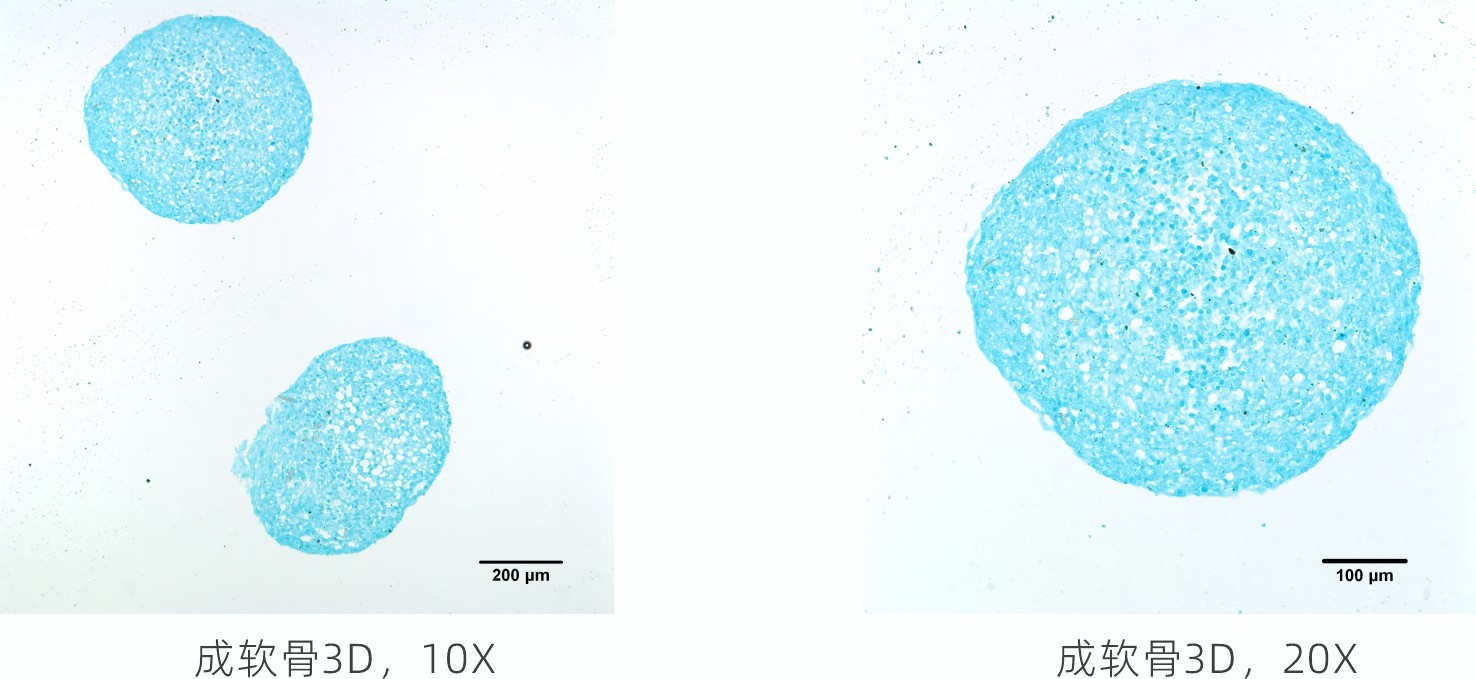

▼成软骨诱导分化(三维)

本品镜下观察可见大面积蓝色着色点,阿利新蓝染色部分显示的是软骨组织中的内酸性粘多糖,说明MSCs具有成软骨能力。